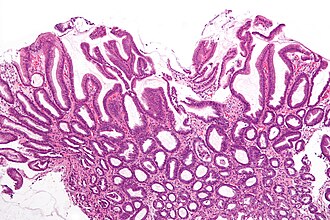

| Caption    = Reactive gastropathy. [[H&E stain]].

Reactive gastropathy. H&E stain.

LM foveolar hyperplasia - esp. tortuosity of glands in the "neck" region (S shaped glands), smooth muscle hyperplasia, scant inflammatory cells, +/-edema, +/-erosions

Features - triad:[5][1]

1. Foveolar hyperplasia.

• Tortuosity of glands in the "neck" region of the gastric glands.

• Associated with "mucin depletion" - cytoplasm not clear -- as is usual.

2. Smooth muscle fibre hyperplasia.

• Abundant eosinophilic lamina propria.

3. Scant acute & chronic inflammatory cells.

Additional features.

• +/-Edema.

• +/-Erosions.